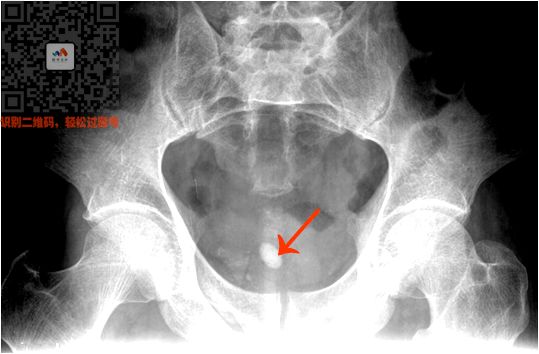

③ 泌尿系统阳性结石

病史:两侧腹部绞痛

特点:

肾和输尿管里面单个或成串的高密度影

看到两侧腹部有白色的圆点

就选肾结石/输尿管结石

看到下腹部的,就选膀胱结石

看图

(双肾结石)

(输尿管结石)

(膀胱结石)